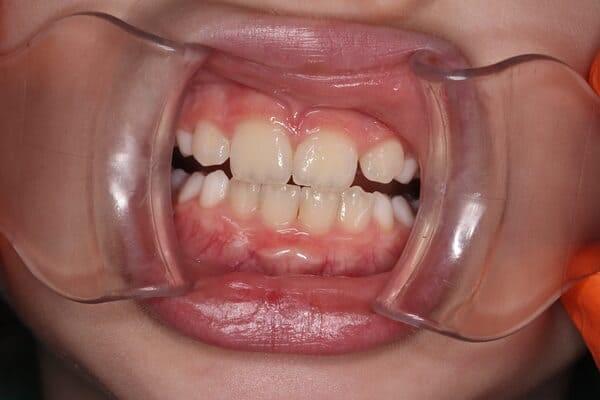

Дівчинка 2 років, але зуби вже мають глибокі ураження із залученням у запальний процес пульпи (“нерва”) зуба. На жаль, так трапляється і зволікати в такому випадку не можна. Було проведено лікування в умовах анестезіологічного забезпечення під контролем досвідченої анестезіологічної команди. Передні зубчики відновлено естетичними коронками, на жувальних зубчиках проведена герметизація фісур, а один вже має глибоке ураження карієсом, тому теж покритий коронкою. Одразу після лікування ясна можуть виглядати дещо травмованими, але за кілька днів вони повністю відновляться.